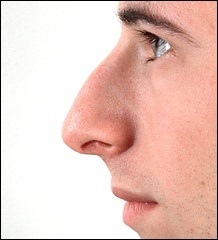

A fénykép a bal oldalon mutatja egy ember tipikus megnövekedett nazális gerinc. Ez jelentősen növeli az orrát előre. A fénykép után a művelet ugyanaz az ember nagyon jól néz ki.